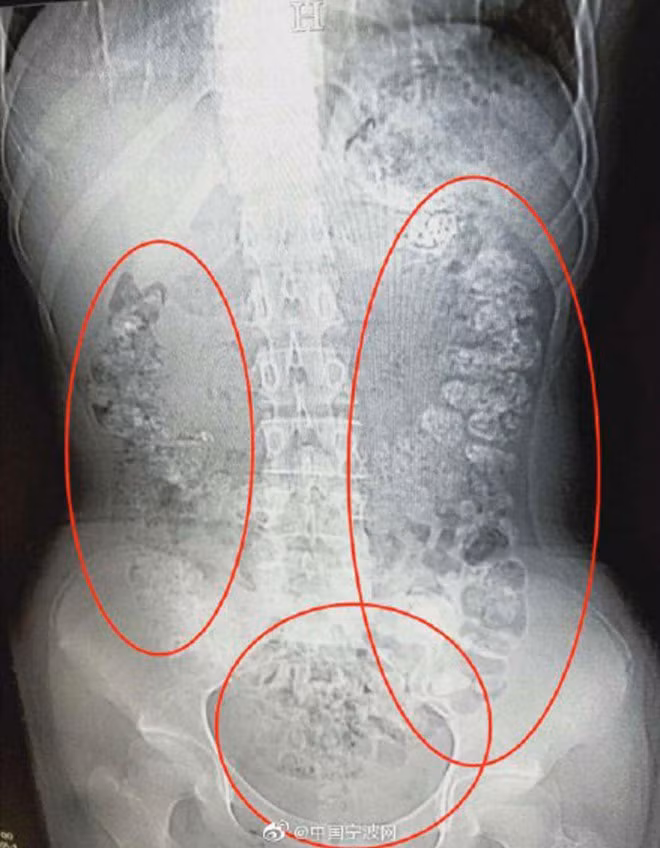

| Ảnh chụp X-quang cho thấy có hàng trăm viên trân châu nằm trong bụng bé gái. Ảnh: Sina. |